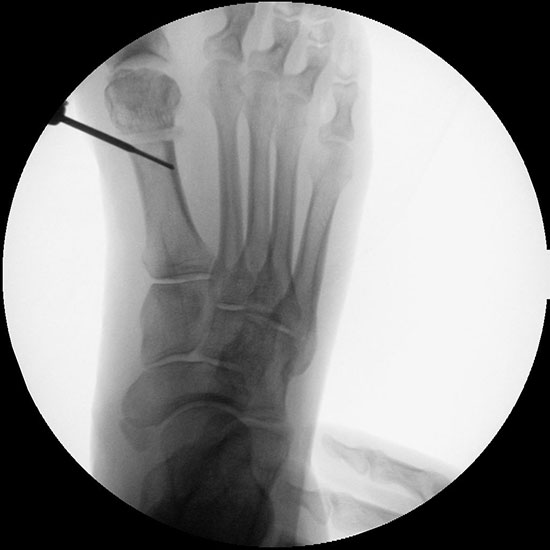

Abbildung 1

• Korrekturpotential größer als beim offenen Chevron, da die Gelenkkapsel als stabilisierendes Element erhalten bleibt und über eine trikortikale Osteosynthese mit zwei kanülierten Schrauben eine Verschiebung bis ca. 80% des Metatarsaledurchmessers möglich ist (Abb. 1).